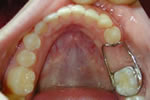

When a primary tooth is lost prematurely the teeth can drift into the new space crowding out the permanent tooth that is supposed to erupt into that space in the future. A space maintainer keeps baby teeth from shifting into the space where the tooth was lost so the permanent tooth can erupt in its natural proper space. As the permanent tooth erupts, Dr. Sidor will remove the appliance. Space maintainers can help eliminate the need for extensive orthodontics in the future.